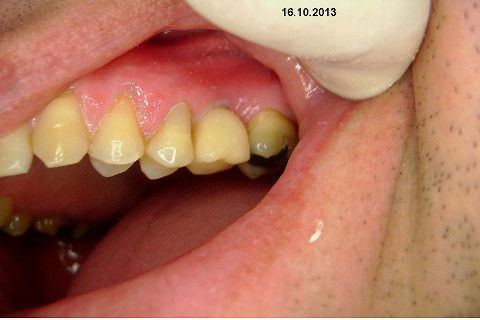

Instalação de um implante em região do 26. Utilizamos um implante cone morse Alvim Neodent 4.3 X 11,5. Foi uma cirurgia muito rápída e minimamente traumática, sem retalho e sutura.

Fotos do caso